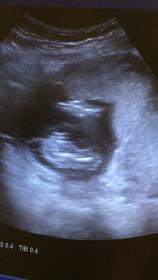

Self-made ultrasound at 16 weeks!

Hi, I am a pediatrician and did try to do an ultrasound on myself (with some watching colleagues) at 15+4 weeks for a potty shot of our third baby.

As we normally use the ultrasound differently I am not experienced with fetusses! Now we have three opinions- I thought the thing between the legs was the cord- one colleague said it SO looked like a penis with scrotum in the one pic (she has a point), two others said "not enough evidence" to decide ;-)

What do you think? We have no nub shot from our (expert) scan at 12+4, only this potty shot. Attachment 41406